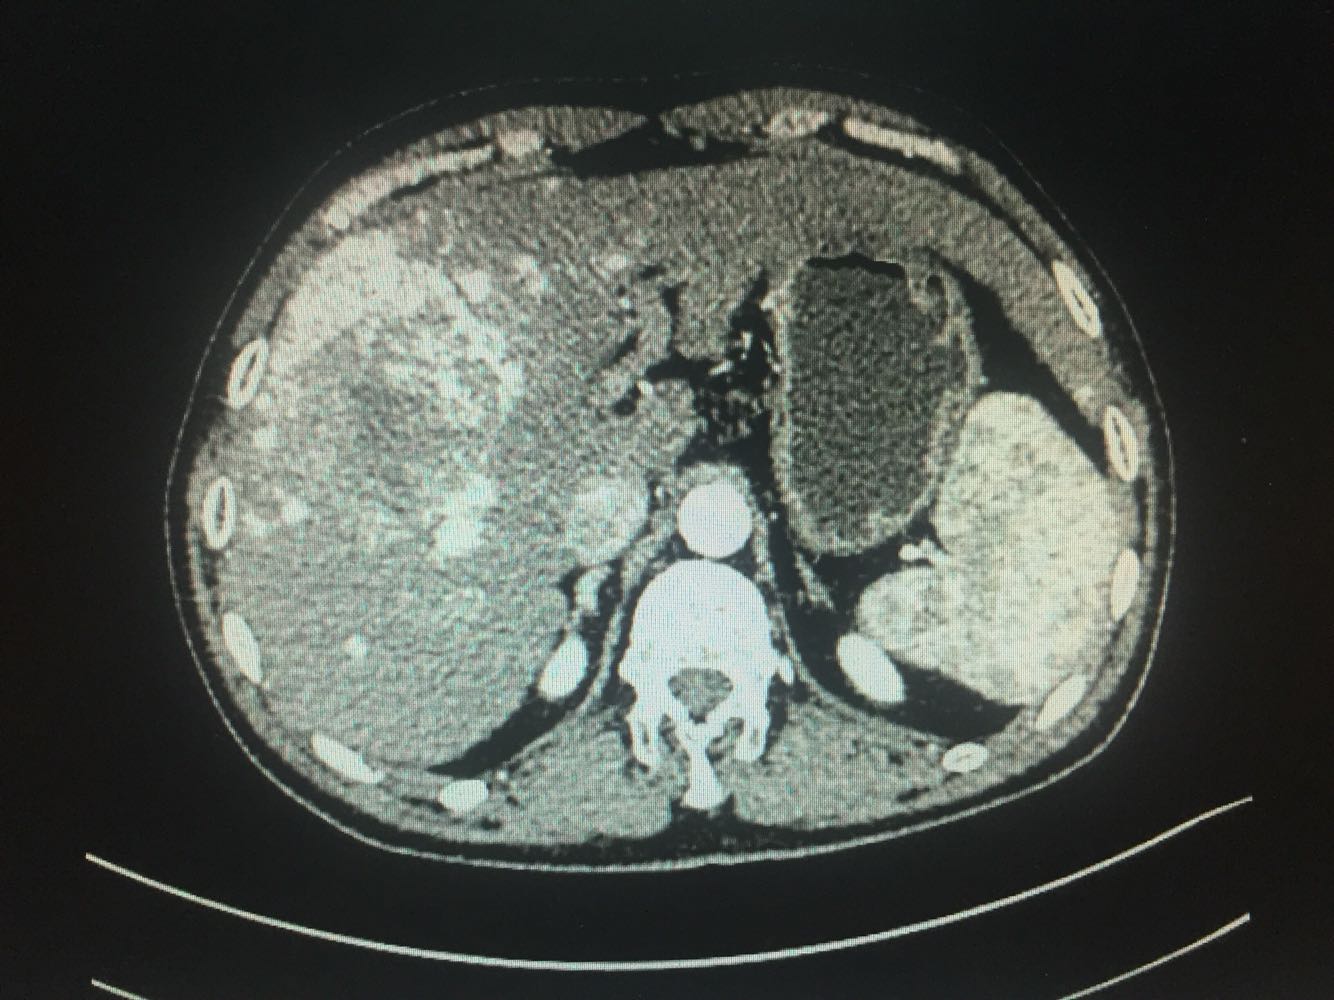

肝癌ct(图)

图片尺寸1433x975